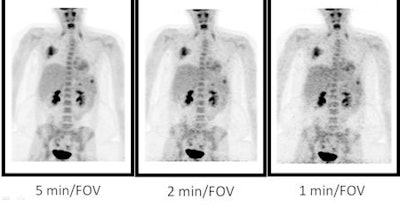

For each patient, multiple datasets with image acquisition times ranging from one minute to five minutes were used to obtain the field-of-view. Fifty-six image volumes were generated, randomized, and reviewed blindly with corresponding CT image volumes by five radiologists. Both overall adequacy and lesion detection accuracy and confidence by body region were evaluated.

"In patients who are greater than 22 kg, our standard acquisition time is five minutes," Sammer said in her presentation. The radiologists "would automatically shorten the data into its lower time points, usually for three, two, and one minute, and [the data] would be stored."

The analysis showed that the average threshold of acquisition time for an adequate PET/CT image for patients weighing less than 22 kg was 2.3 minutes. In patients weighing between 22 and 70 kg, the average threshold of acquisition time was two minutes, and for patients weighing more than 70 kg, the time was three minutes.

Lesion detection accuracy and diagnostic confidence was not degraded from five minutes to one minute for the field-of-view for abdominal lesions, but chest lesion detection became less accurate when imaging acquisition was reduced more than 30%.

| PET/CT scan of an 18-year-old, 94 kg (207 lb) female patient who was imaged for the staging of osteosarcoma. The five-minute image acquisition time was considered adequate, as was the image obtained at three minutes. Images acquired at two minutes and one minute were deemed inadequate. However, lesion detection was degraded at one minute and was preserved at two minutes and longer. The adequate field-of-view for this patient was three minutes, so dose potentially could have been reduced by 40% to 60%. Image and information courtesy of Marla Sammer, MD. |